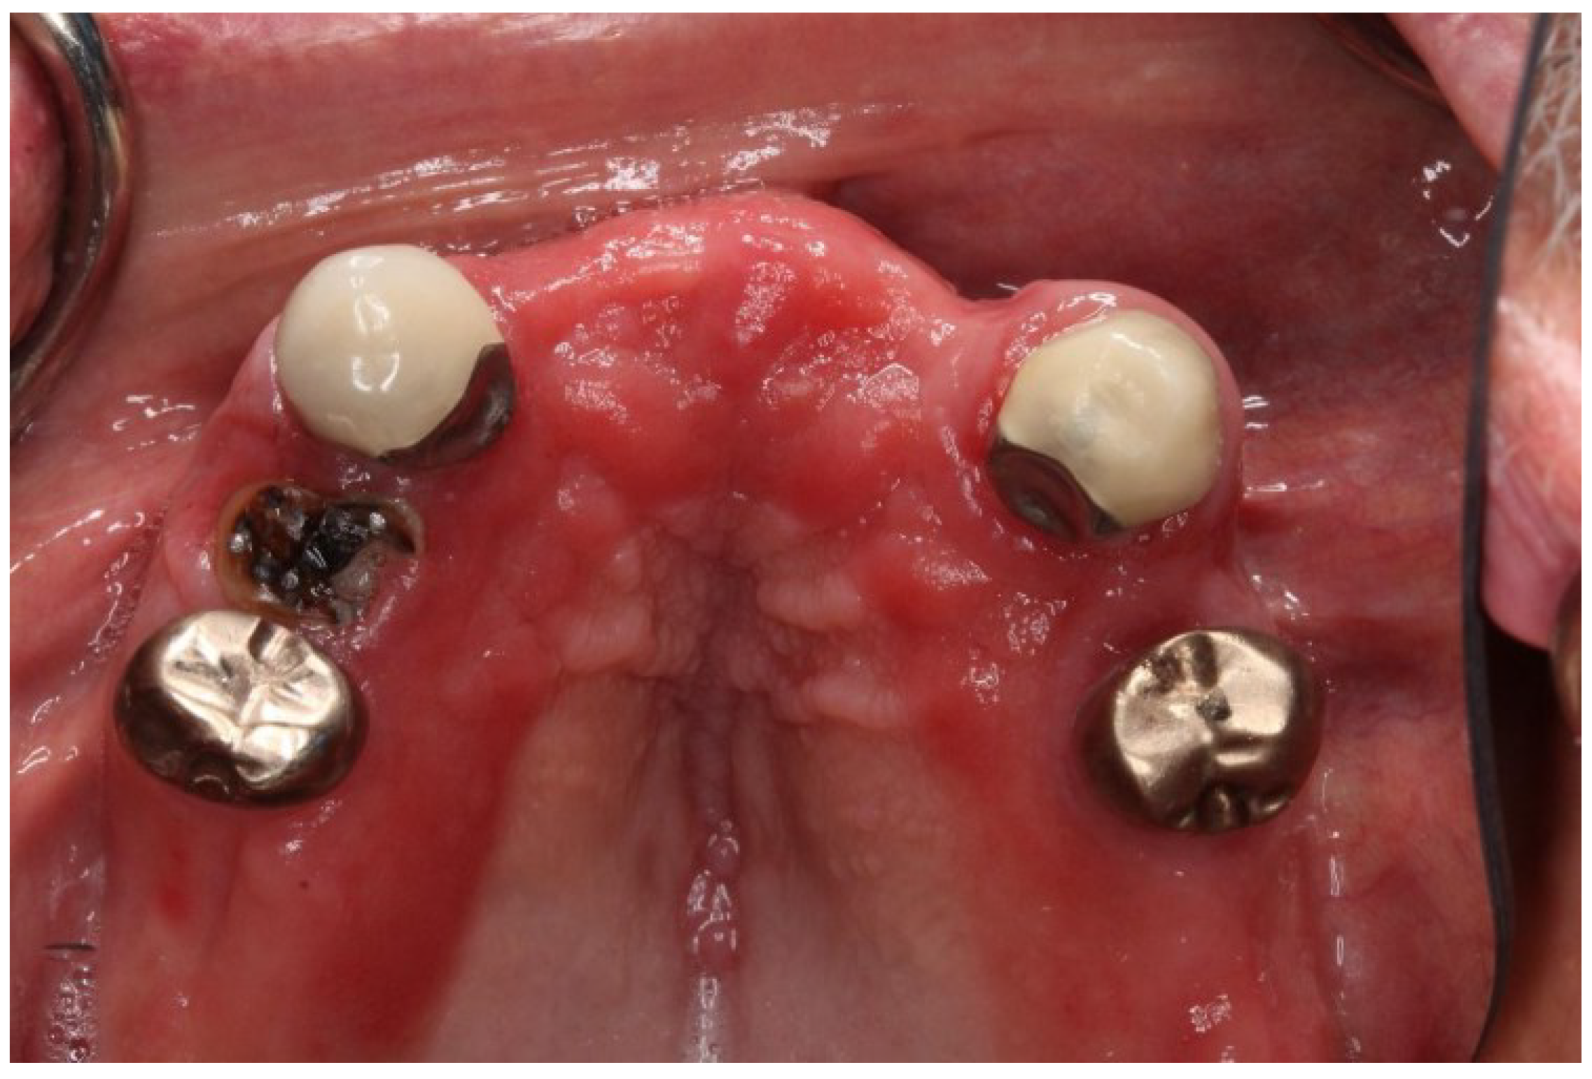

Denture Stomatitis

5. Pathogens in Denture Stomatitis